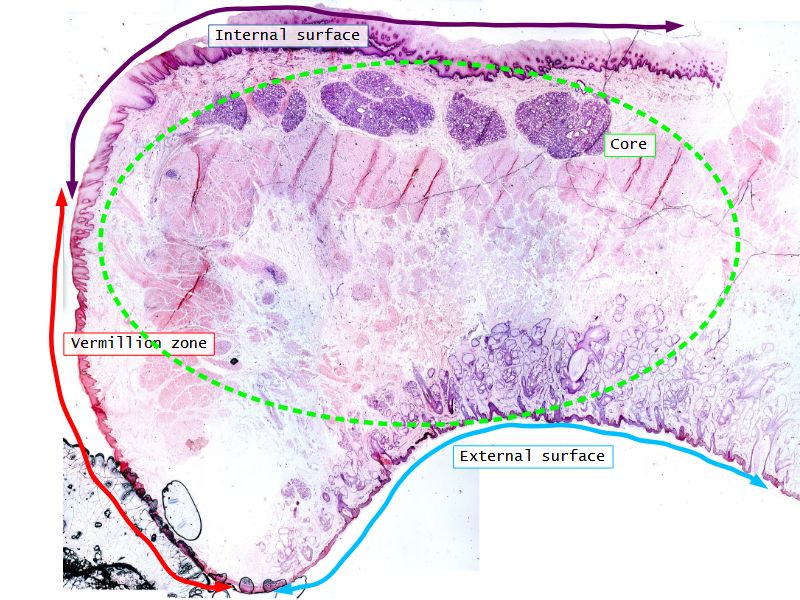

Fill in all the missing labels, and assess as you move through the slides. Answers on the down slide. It is important to do this using pen and paper, and not just glance through the images.